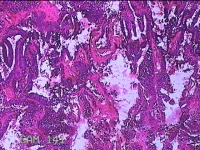

性别

女

年龄

34岁

临床诊断

异常子宫出血

一般病史

阴道不规则流血1月余。

标本名称

宫内物

大体所见

灰白暗红色不规则碎组织4.8x4.3x1.3cm一堆。

单纯性增生,局部呈复杂型增生